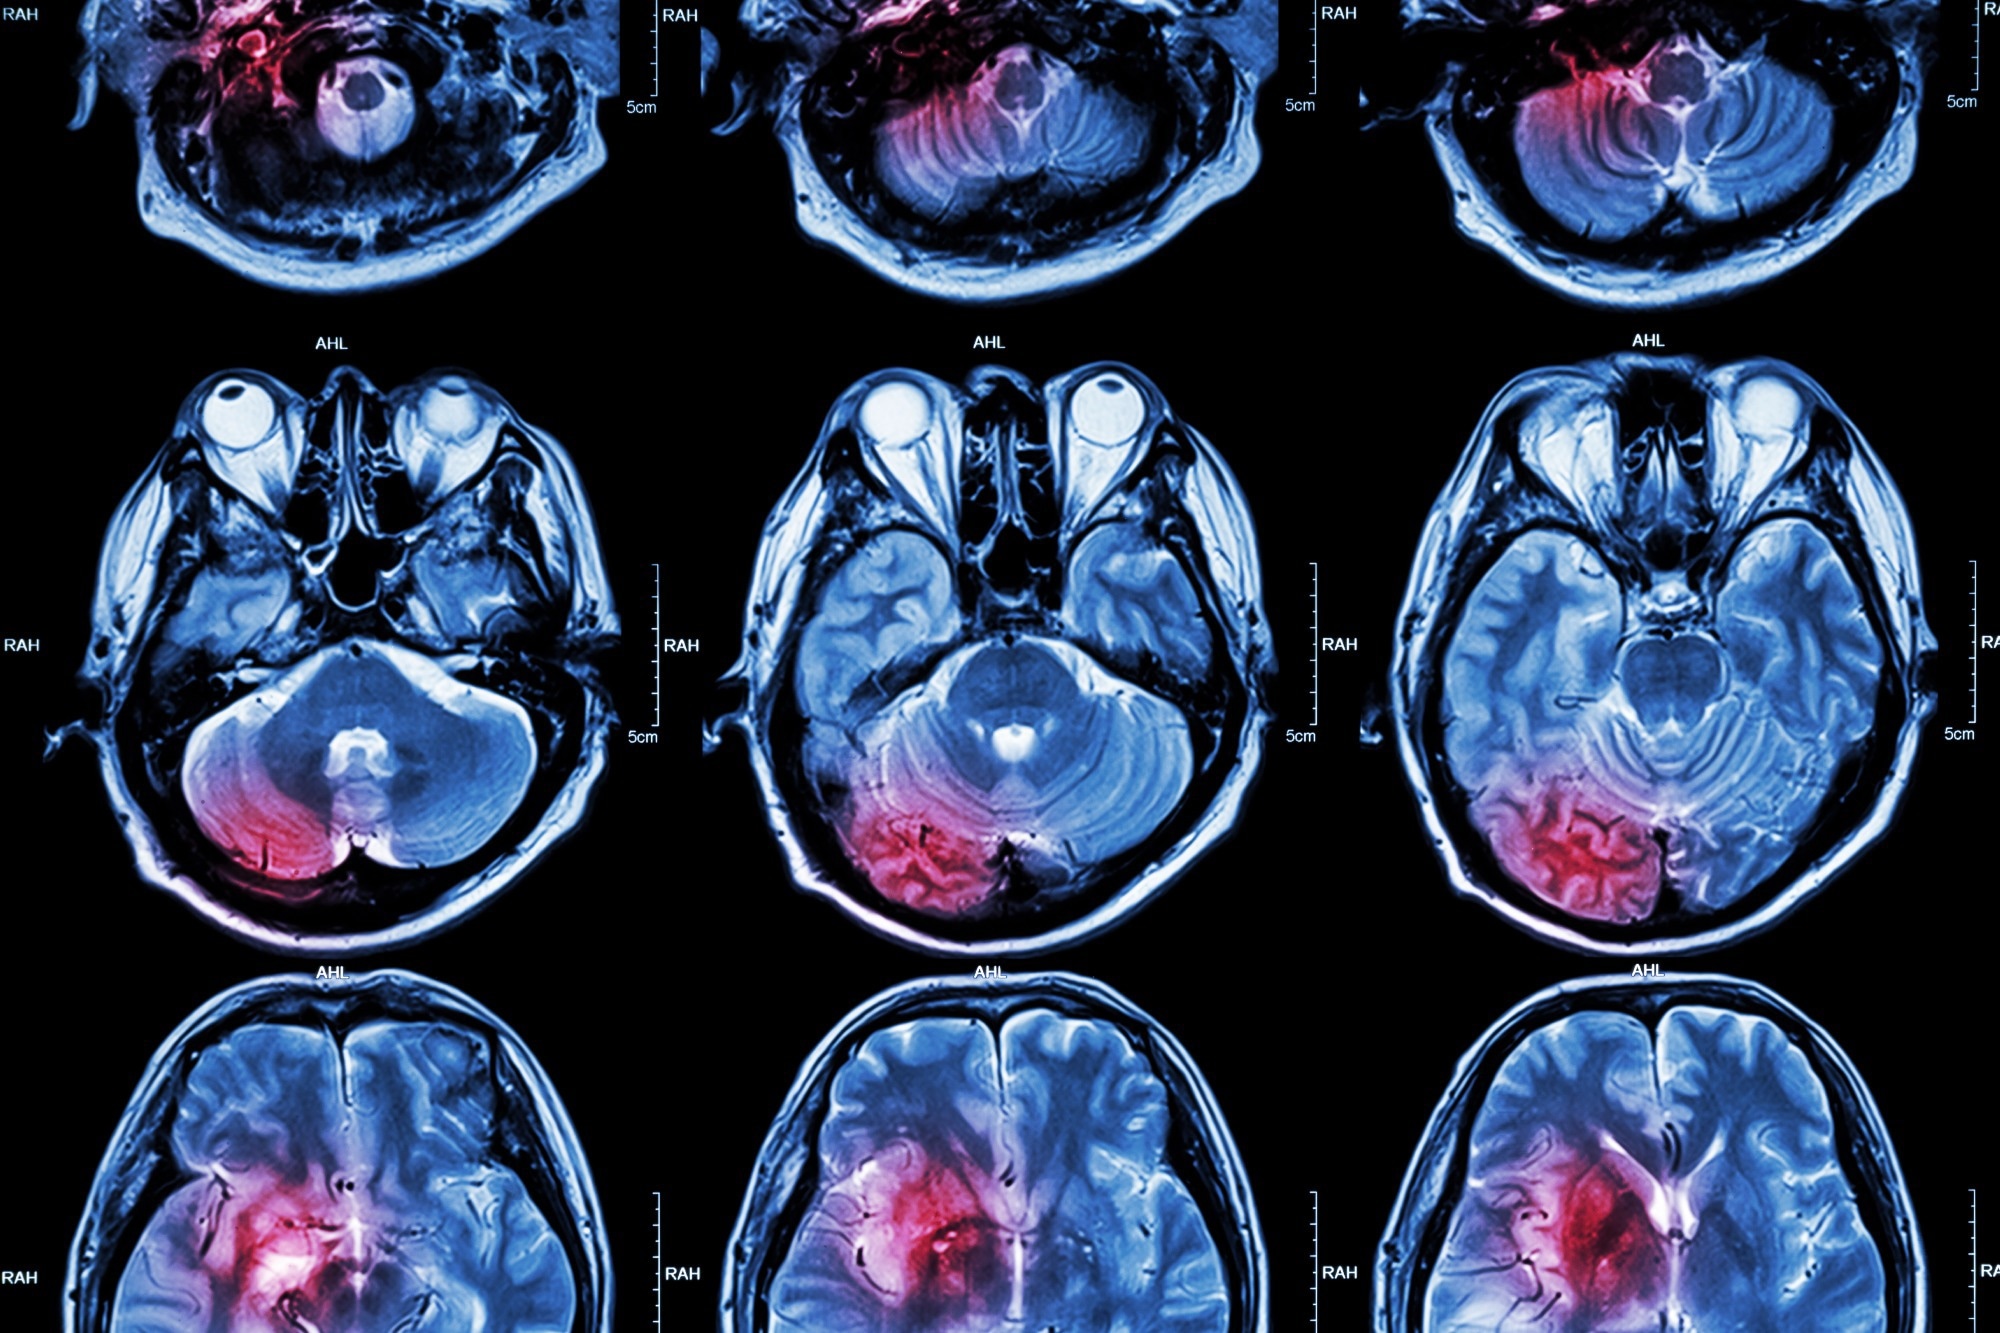

Study: The third Intensive Care Bundle with Blood Pressure Reduction in Acute Cerebral Haemorrhage Trial (INTERACT3): an international, stepped wedge cluster randomised controlled trial. Image Credit: PuwadolJaturawutthichai/Shutterstock.comStudy: The third Intensive Care Bundle with Blood Pressure Reduction in Acute Cerebral Haemorrhage Trial (INTERACT3): an international, stepped wedge cluster randomised controlled trial. Image Credit: PuwadolJaturawutthichai/Shutterstock.com